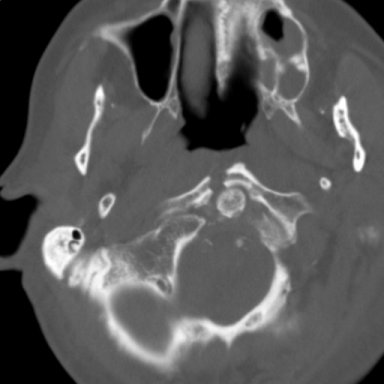

Return to Jefferson Fracture